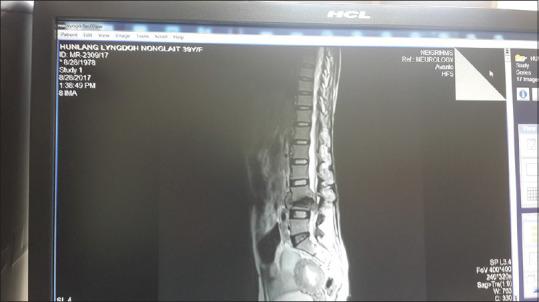

Though tuberculosis is commonly seen in India, uncommon manifestations like peripheral gangrene is also a possibility. Here we present a case of spinal tuberculosis, with peripheral gangrene.

虽然结核病在印度很常见,但像周围坏疽这样的罕见表现也有可能出现。在此,我们报告一例伴有周围坏疽的脊柱结核病例。